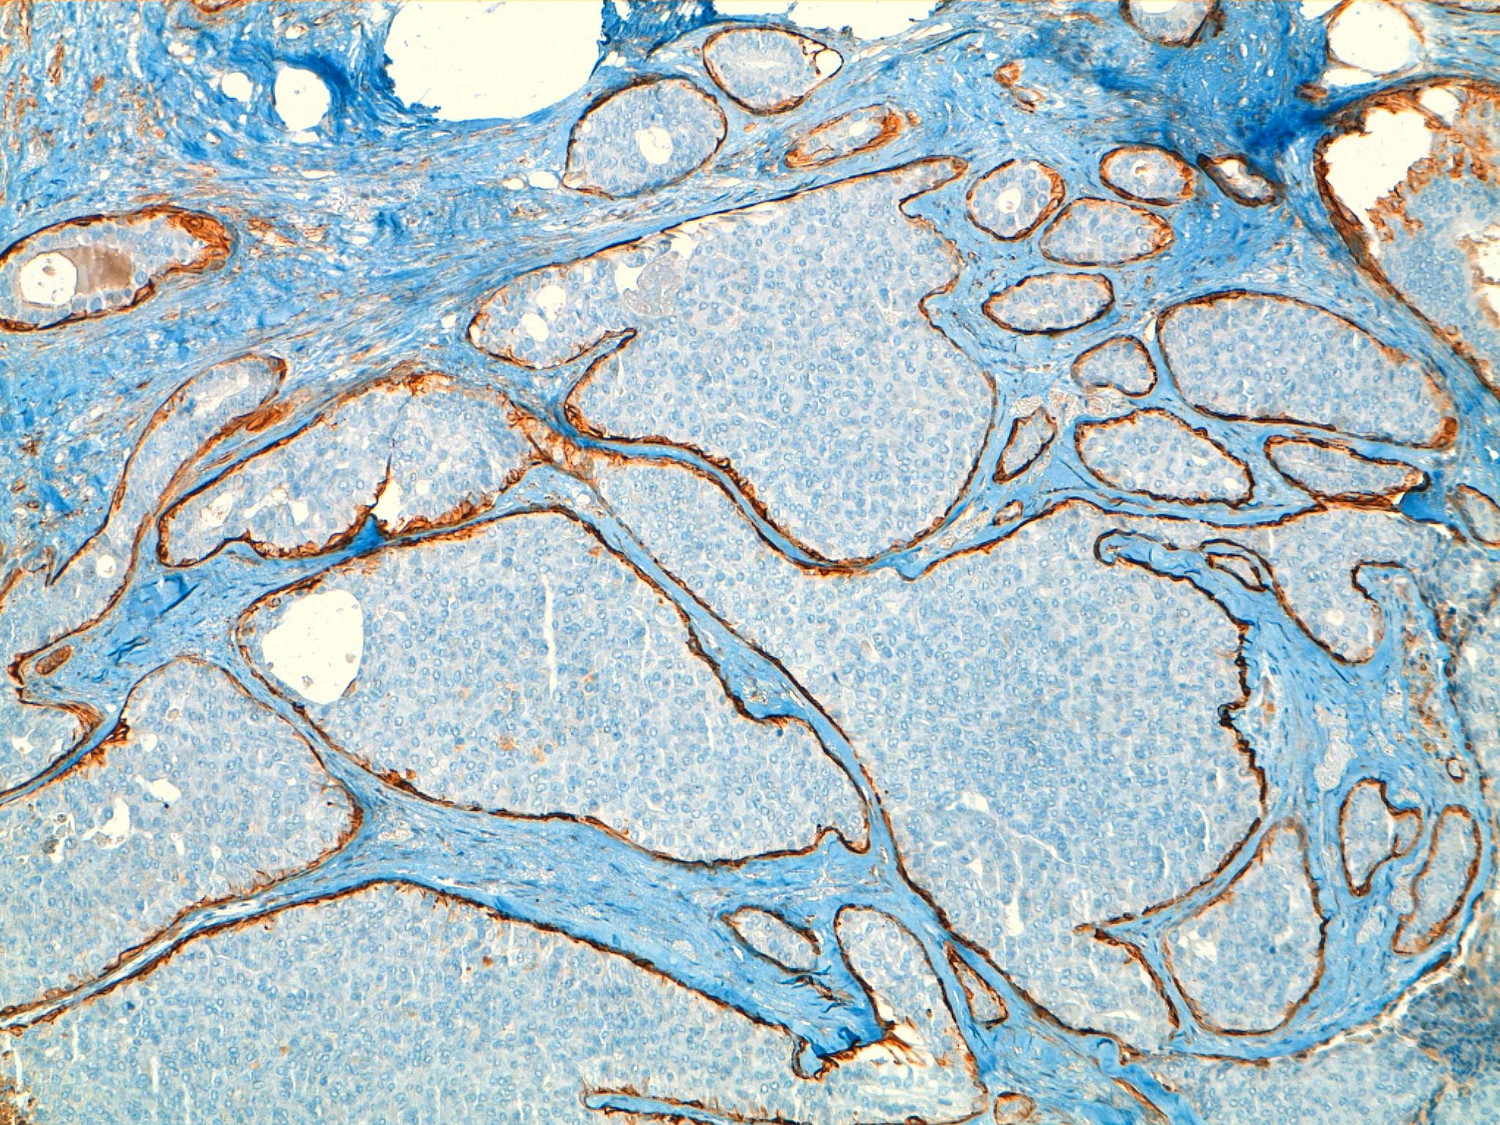

Given the findings, a deferred biopsy was decided upon. Pathology reported the existence of a cystic lesion of 13 mm in the lumpectomy sample. Histological sections showed a cystically dilated duct, neoplastic proliferation within an interior of solid and papillary growth with a delicate fibro vascular stroma and small cells with mild atypia and occasional mitotic figures. In the periphery of the cyst tumorous nests were observed consistent with micro-infiltration areas, and confirmation of the absence of myoepithelial cells with techniques of immunohistochemistry (actin and collagen IV). The immunohistochemistry was positive for hormone receptors (estrogen and progesterone), absence of expression of HER-2 and pof 53 negative. The pathological diagnosis was intracystic papillary carcinoma with solid areas of micro-infiltration but without being able to evaluate the margins of the resection (Fig. 2).

Figure 2

Characteristic labeling of cells with actin HHF35 periphery of nests in areas of in situ component.